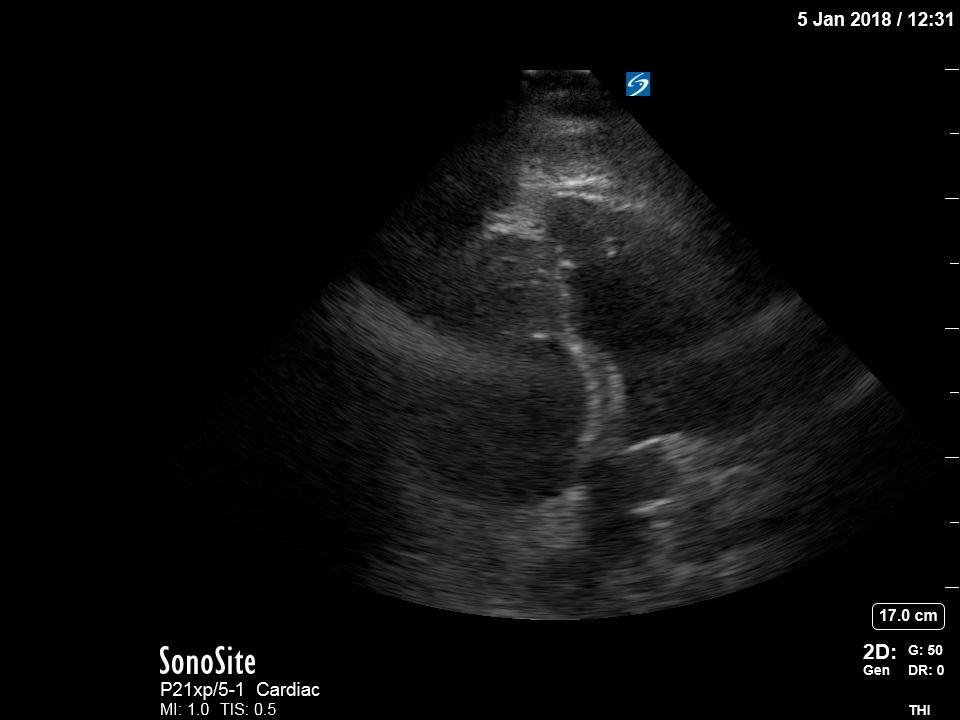

Bedside echocardiography four chamber view revealed enlarged right ventricular (RV) to left ventricular (LV) ratio (greater than 1) on apical four-chamber view (see red and blue outlines respectively). The right atrium is not clearly delineated in this image and therefore is not outlined. One can also rule out a large pericardial effusion as the cause of her dyspnea, since there is no large hypoechoic collection surrounding the heart on either four- chamber view or parasternal long view.

Point of care ultrasound is a powerful tool that can aid in the diagnosis of undifferentiated dyspnea. Right ventricular size is one parameter that can signify right heart strain possibly due to an increase in resistance in the pulmonary vasculature. The normal RV should be approximately two-thirds the size of the left ventricle. Any RV between two-thirds and equal to the size of the LV is considered moderately dilated, and any RV greater in size than the LV is considered severely dilated.1,2 The RV to LV size ratio is best measured from the apical four-chamber view. Right ventricular shape will also change as afterload increases in the pulmonary circuit. As pulmonary vascular resistance increases, the RV (which has significantly less myocardium and thus greater compliance as compared to the LV) begins to lose its typical triangular shape and takes on a more rounded appearance.3 Likewise, the intraventricular septum becomes flattened during early diastole due to higher RV:LV pressures causing the LV to take on a “D” shaped appearance. These findings, collectively referred to as signs of “right heart strain,” typically improve with resolution of the clot burden.4